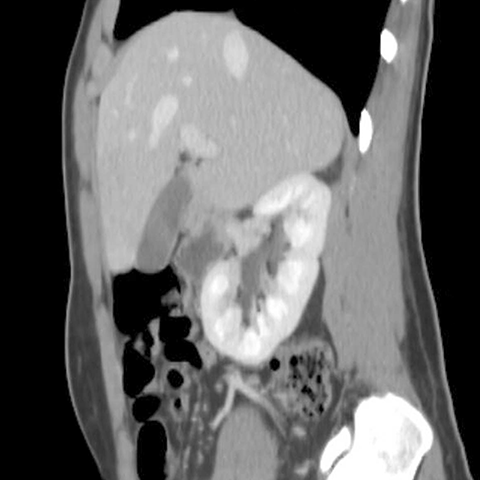

Right kidney, sagittal view (CT) [9 of 9]